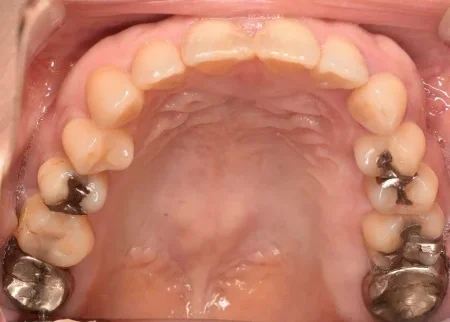

セラミック 2023.0240代女性「銀歯を白くしたい」奥歯の複数の詰め物と被せ物を全てセラミックとジルコニアで白く作り直した症例